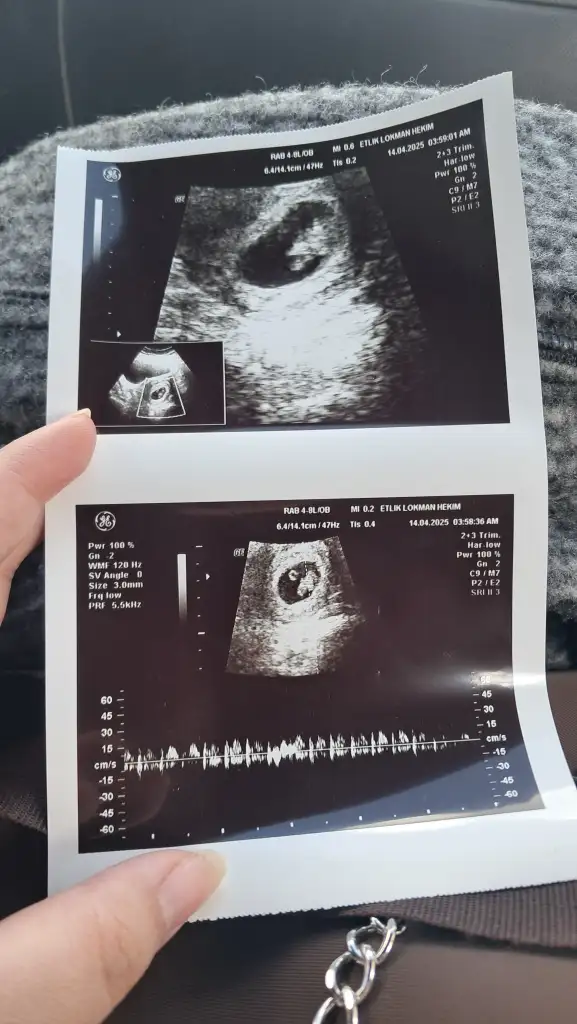

ay benimkini de yorumlar mısınız 🙏🏻 karından ultrason

Bu bebiş büyümüş tahmin etmek zor ☺️ ama içimden erkek geçti 🌸